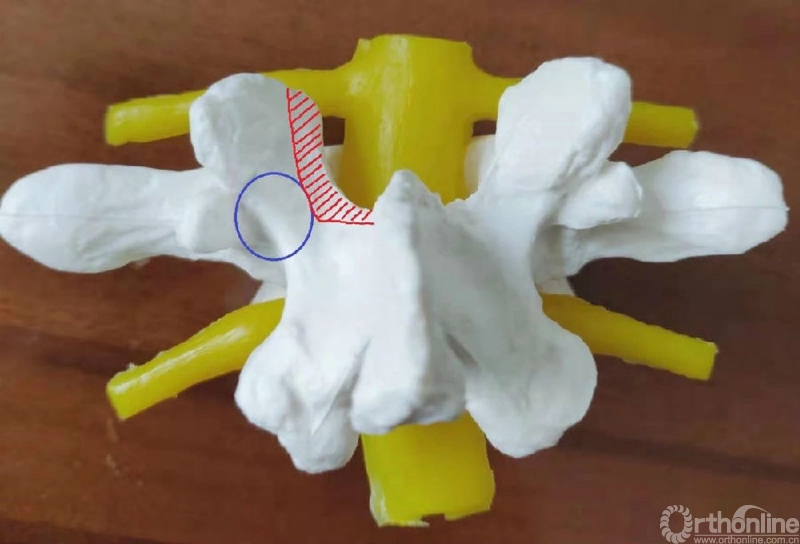

延伸阅读:UBE同侧侧隐窝减压范围的问题

UBE处理椎管狭窄病例时,对于侧隐窝狭窄的患者,同侧减压范围与椎弓根内缘平齐即可。

从标本上看,椎弓根其实就位于终板的下方,这是术中判断椎弓根位置的解剖标志。

与椎间盘的下缘平齐即是椎弓根的上缘。

去除部分椎板上缘骨质尤其是与上关节突结合的部位利于黄韧带的切除及椎弓根内壁的显露。这个部位显露神经根的风险最小。